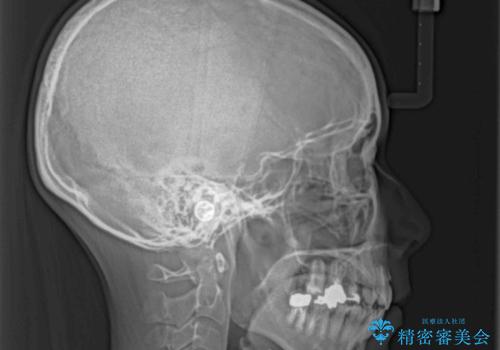

上下の咬み合わせは上顎歯列全体が歯1本分前にずれている状態であり、さらに上顎歯列はV字型に尖っていたため、上下前歯は全く接触していない状態でした。

上顎左右第一小臼歯を抜去して、ワイヤー装置にて口元の突出感を改善するよう矯正治療を行うこととしました。

上顎前歯の歯軸が顕著に改善され、非常に口の閉じやすい歯列に仕上げることができました。